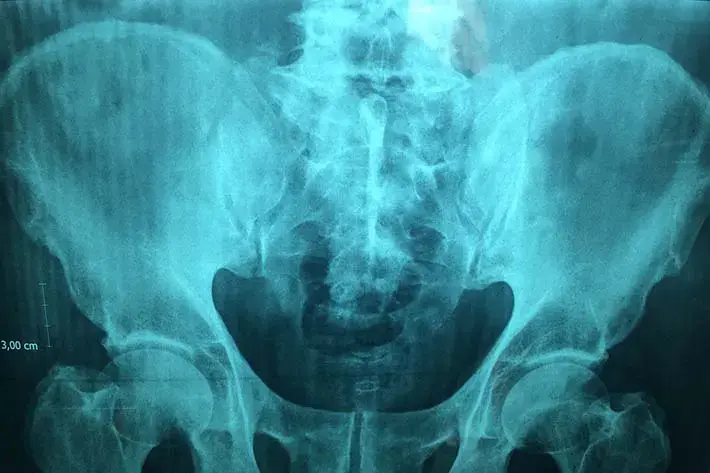

X-ray or radiography uses a very small dose of ionizing radiation to produce pictures of the body’s internal structures. X-rays are the oldest and most frequently used form of medical imaging.

They are often used to help diagnose fractured bones, look for injury or infection and to locate foreign objects in soft tissue.